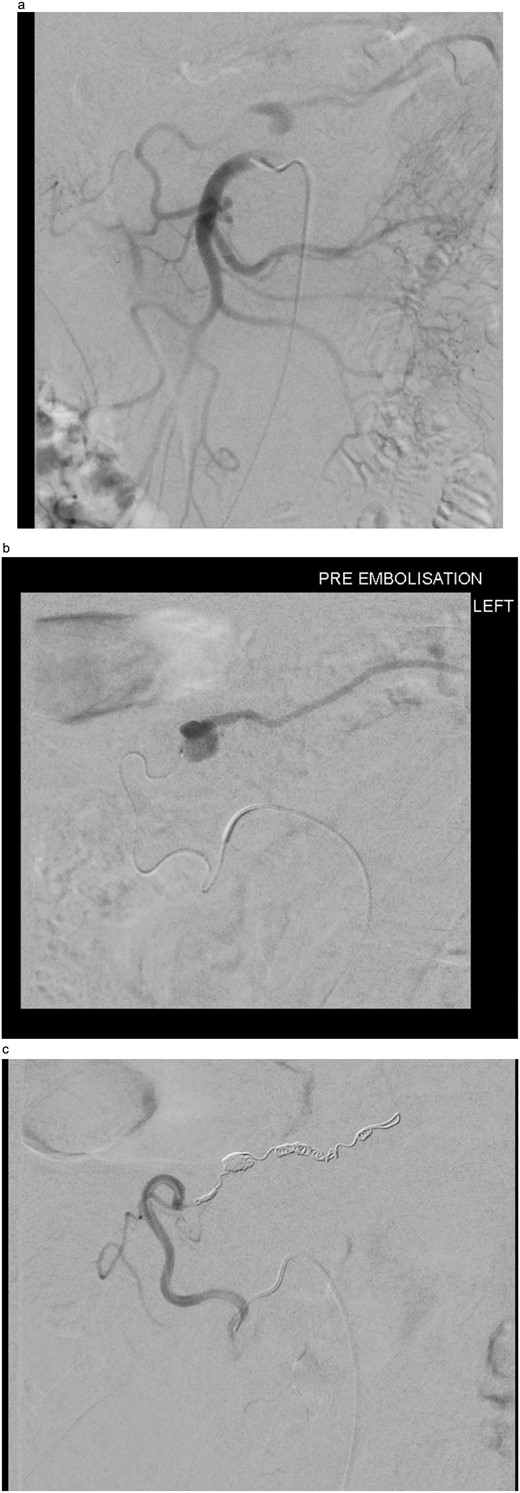

The two-week interval CTA showed that the pseudoaneurysm had increased in size to 2.1 × 1.8 × 1.8 cm (AP × TR × CC) (see Fig. 2). Whilst acknowledging the high risk of gut ischemia, the MDT agreed that intervention was necessary to avoid the risk of rupture. Eight weeks after initial pseudoaneurysm diagnosis, he underwent successful embolization of the MAoD. The embolization procedure was challenging due to tortuosity of the vessel and at the time, deemed too tortuous to stent on table, therefore embolization performed with microcoils (see Fig. 3). He remained clinically asymptomatic with a soft abdomen and had an overnight stay with the general surgery team on standby. His lactate remained insignificant overnight. He opened his bowels and managed a normal diet and was therefore discharged home the following day.

Interval CT angiogram demonstrating enlargement of the false aneurysm (2.1 × 1.8 × 1.8 cm).

(a) Digital subtraction angiogram (DSA) image taken from the SMA, demonstrating the pseudoaneurysm arising from the marginal artery of Drummond. (b) Microcatheter within the marginal artery of Drummond demonstrating the pseudoaneurysm. (c) Post-embolization image with four microcoils and successful occlusion of the pseudoaneurysm.